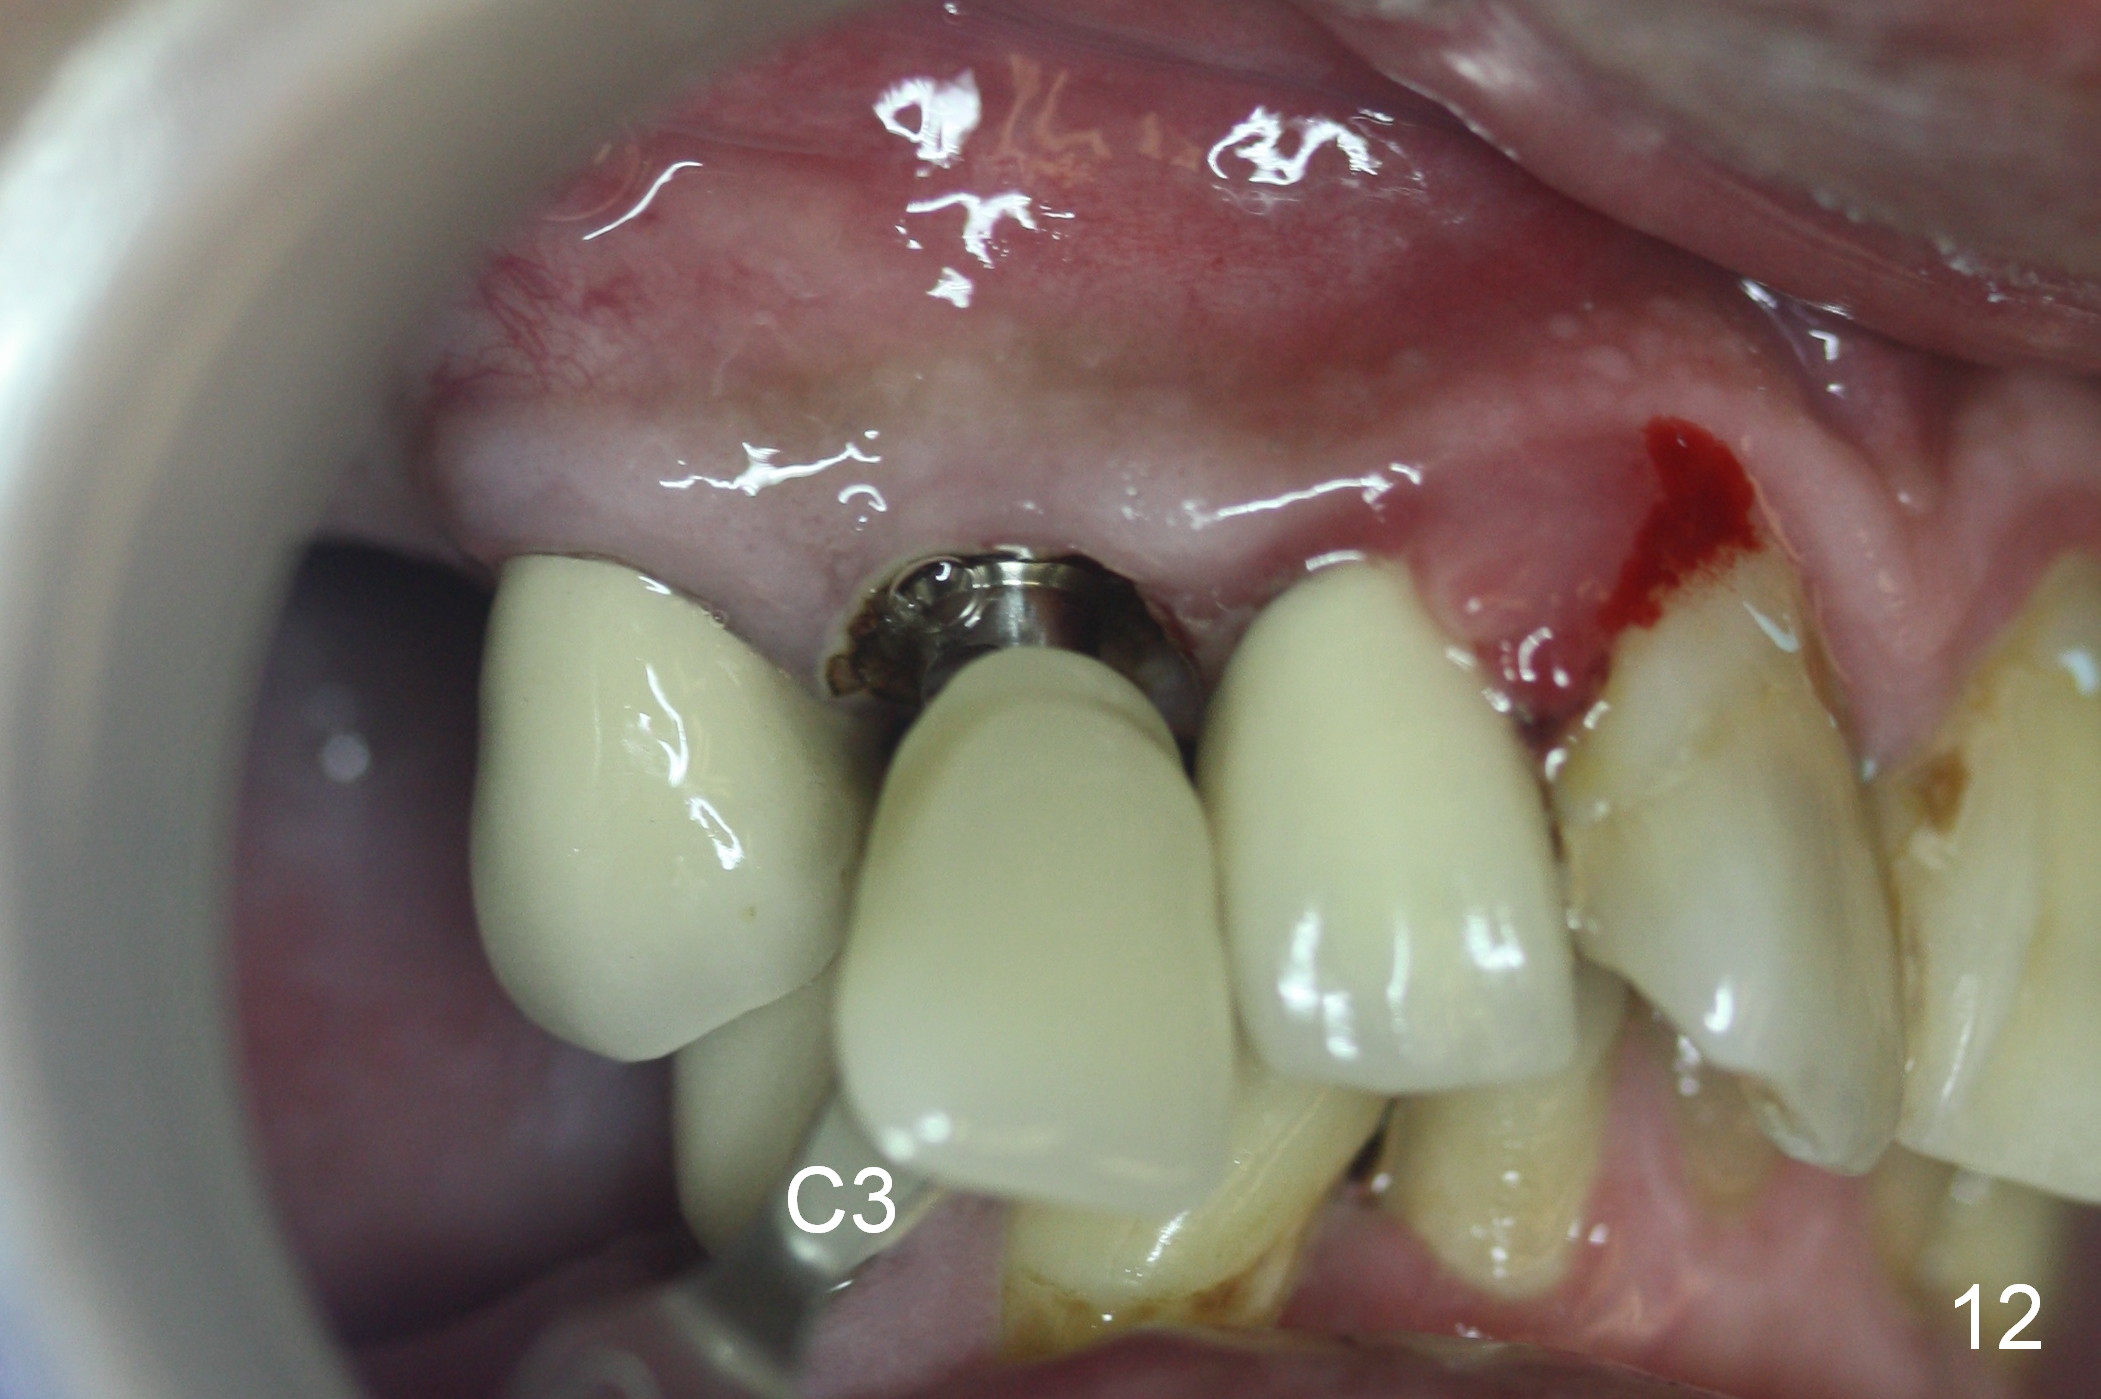

Three months postop, the provisional is dislodged (Fig.7-9). The mesial gingiva is hypertrophic buccally (Fig.8 *) and lingually (Fig.9 *). There appears to biologic width violation (Fig.5). The abutment should be changed to the one with smaller in diameter and longer in cuff (4.5x5(4) mm) with the buccal margin reduction.

Six days post provisional reline, the mesial papilla erythema has subsided substantially; the abutment is changed to 4.5x5(2) with Diode gingivectomy (Fig.10-12).